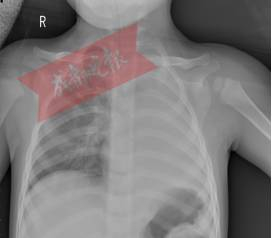

7月29日晚,成都1岁多的女孩豆豆(化名)经四川省妇幼保健院急诊科绿色通道快速进入重症医学科抢救。一天前还是活蹦乱跳的孩子,突然被送进重症监护室,而更令所有人大吃一惊的是,胸片显示,孩子的左肺竟然“不见了”?!

重症医学科副主任谢成告诉记者,接诊的时候豆豆气喘急促、口唇发绀,左侧肺部呼吸音消失,各项的生命指征都不好。重症医学科医护团队立即给豆豆气管插管、呼吸机辅助通气治疗,在维持孩子的氧合前提下,放射科顺利完成了床旁胸片检查,而胸片的结果却让在场所有人震惊:孩子的左肺竟然“不见了”?!

肺从片子上消失,医学上称为“白肺”。正常的肺部有空气进入,在 CT 片上是呈影的。“白肺”,即肺部显影呈一大片的白色状,起因一般是重症肺炎或者大量的胸腔积液。但是豆豆并没有肺部疾病史,究竟是什么原因呢?重症医学科副主任谢成告诉记者:“当时反复追问家属是否有异物呛入病史,但是孩子的父母都坚决否认。”